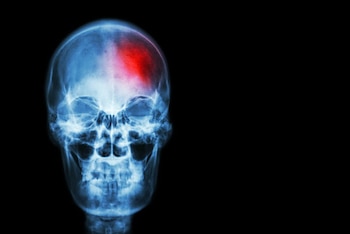

"El ictus es una enfermedad cerebrovascular que se produce cuando el flujo de sangre que llega al cerebro se interrumpe o se reduce. Existen dos tipos principales de ictus: el ictus isquémico, que representa aproximadamente el 80% de los casos, y el ictus hemorrágico, que supone el 20% restante. Mientras que el ictus isquémico se produce cuando un trombo impide u obstaculiza la llegada de sangre al cerebro, el ictus hemorrágico se genera por la rotura de alguno de los vasos sanguíneos del cerebro. Pero en ambos casos el tiempo de actuación es determinante", explica la doctora Mª Mar Freijo, Coordinadora del Grupo de Estudio de Enfermedades Cerebrovasculares de la SEN.